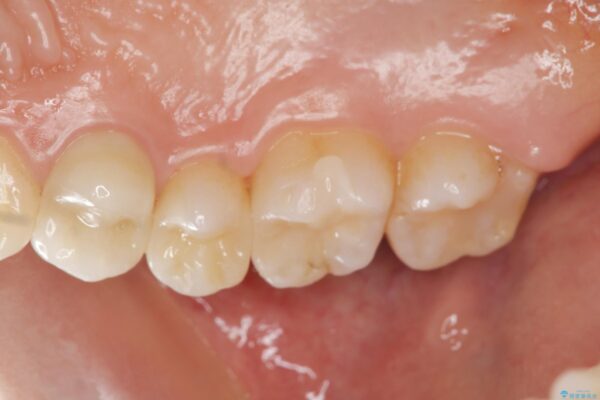

治療後

銀歯を除去してのセラミック治療[ メタルフリー ] 治療後画像 銀歯を除去してのセラミック治療[ メタルフリー ] 治療後画像 銀歯を除去してのセラミック治療[ メタルフリー ] 治療後画像